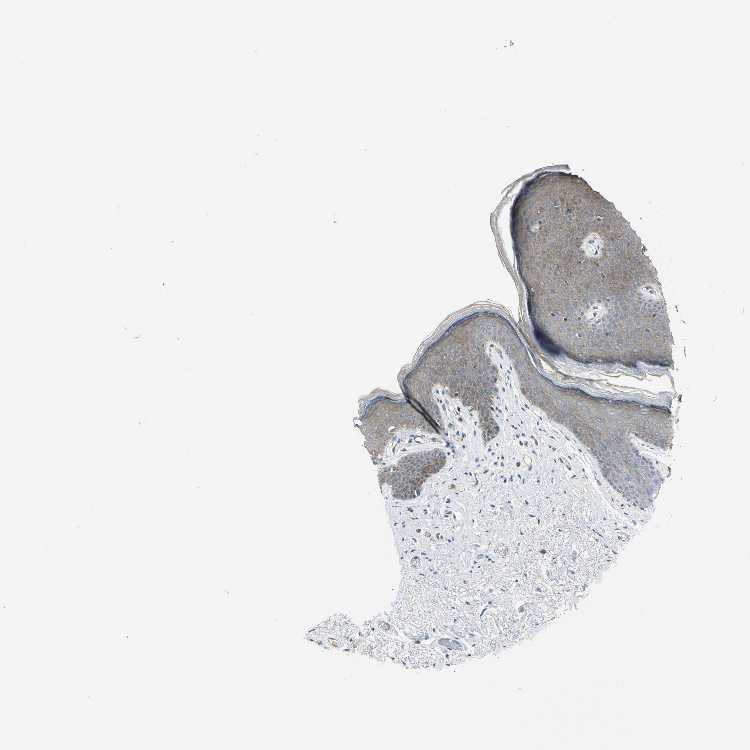

TISSUE PRIMARY DATA SKIN Show tissue menu

SKIN 1 - Antibody stainingi

Antibody staining in the annotated cell types in the current human tissue is reported as not detected, low, medium, or high, based on conventional immunohistochemistry profiling in selected tissues. This score is based on the combination of the staining intensity and fraction of stained cells.

Each image is clickable and will lead to virtual microscopy that enables deeper exploration of all samples and also displays staining intensity scores, fraction scores and subcellular localization as well as patient and tissue information for each sample.

SKIN 2 - Antibody stainingi